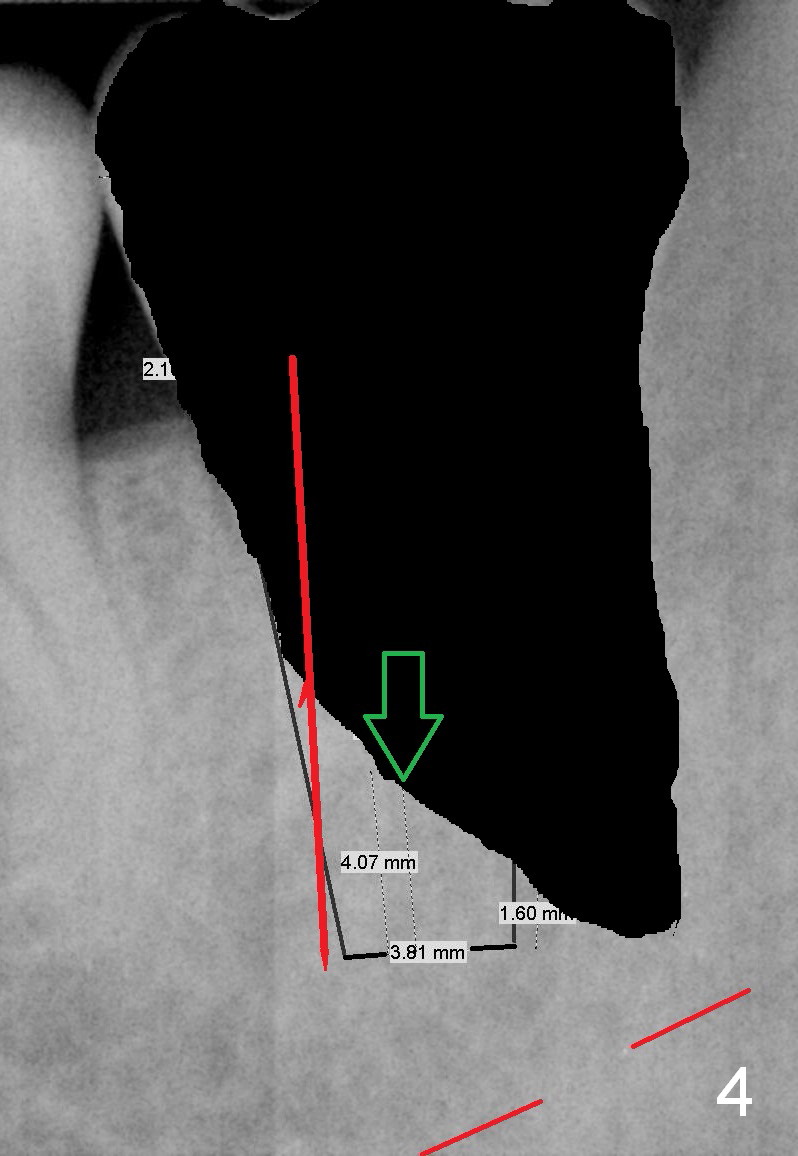

A 34-year-old man has distal deep caries of the lower 2nd molars. Root canal therapy turns out to be difficult on the right side due to bleach leakage. It would be also difficult to restore the distal defect. Finally he agrees to have extraction and implant. The result is good. He is ready to accept the same treatment for the left 2nd molar (Fig.1 (arrowheads: caries)). Metronidazole will be used for socket decontamination. Place a 5.9x10 mm bone-level implant 2 mm below the mesial crest (hopefully at the same level of the buccal crest) so that there is enough height to place an abutment (Fig.2). The apex of the implant is placed mesial to that of the root, since there is more bone, away from the superior border of the Inferior Alveolar Canal (red dashed line). The osteotomy is to be initiated in the middle of the mesial slope obliquely, more mesial (Fig.3 red line) than the center of the implant (green arrow). Once the lamina dura is penetrated, change the trajectory along the future long axis of the implant (Fig.4 red line). The depth will be 14 mm from the mesial gingival line (Fig.2). As the diameter of drills increases, the osteotomy tends to shift distal (Fig.5 pink arrow).

In fact, RCT is tried. Fourteen months later, the tooth remains symptomatic with mobility (Fig.6). Due to the distal defect caused by the 3rd molar (Fig.6,7 arrowheads), the implant should be placed as mesial and deep as possible.